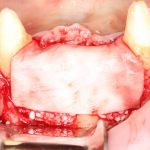

Рекомендации по установке имплантов. Для всех. Часть V.